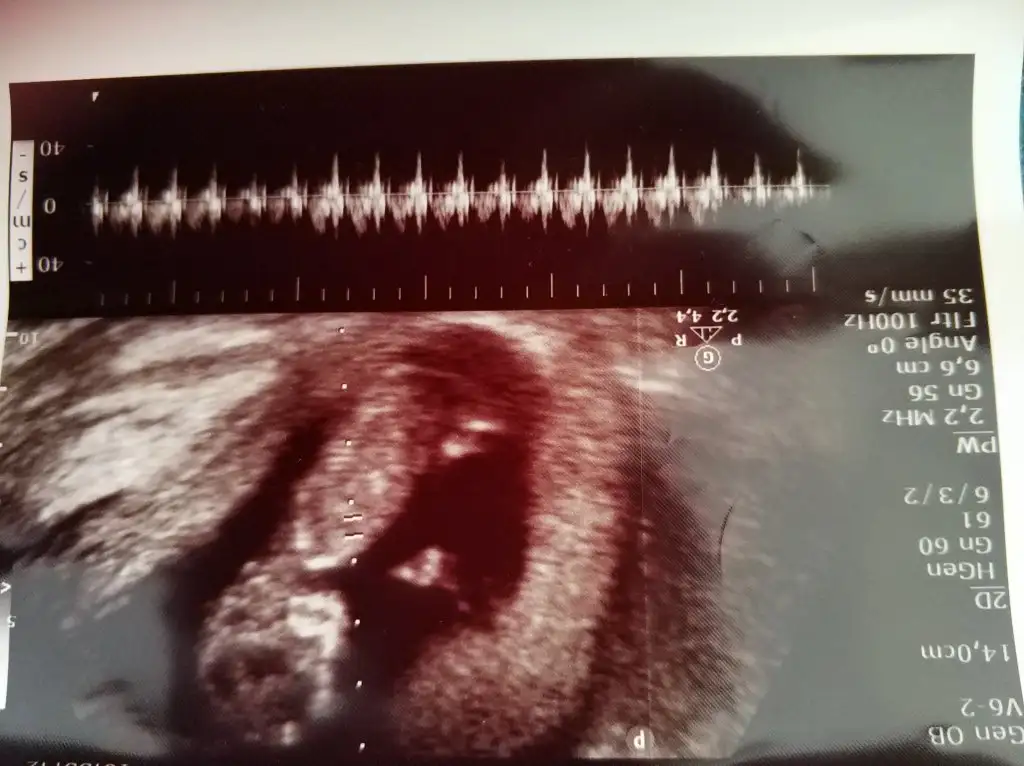

Emin olamadım renklilerde sırtı dönük diğeri çok parlak sanki sanki kız ama emin değilimHerkese merhaba bebeğim burda 12+6 cinsiyetini öğrenemedim malesef gostermedi. Banada yardımcı olursanız çok sevinirim![]()

Teşekkür ederim bu ikinci bebegim ilki kızdı ve karnımın sağ tarafındaydi bu da sol tarafında çok etkiler mi emin değilim ama hayırlısı bakalım inşaAllah bu cuma gösterirEmin olamadım renklilerde sırtı dönük diğeri çok parlak sanki sanki kız ama emin değilim![]()